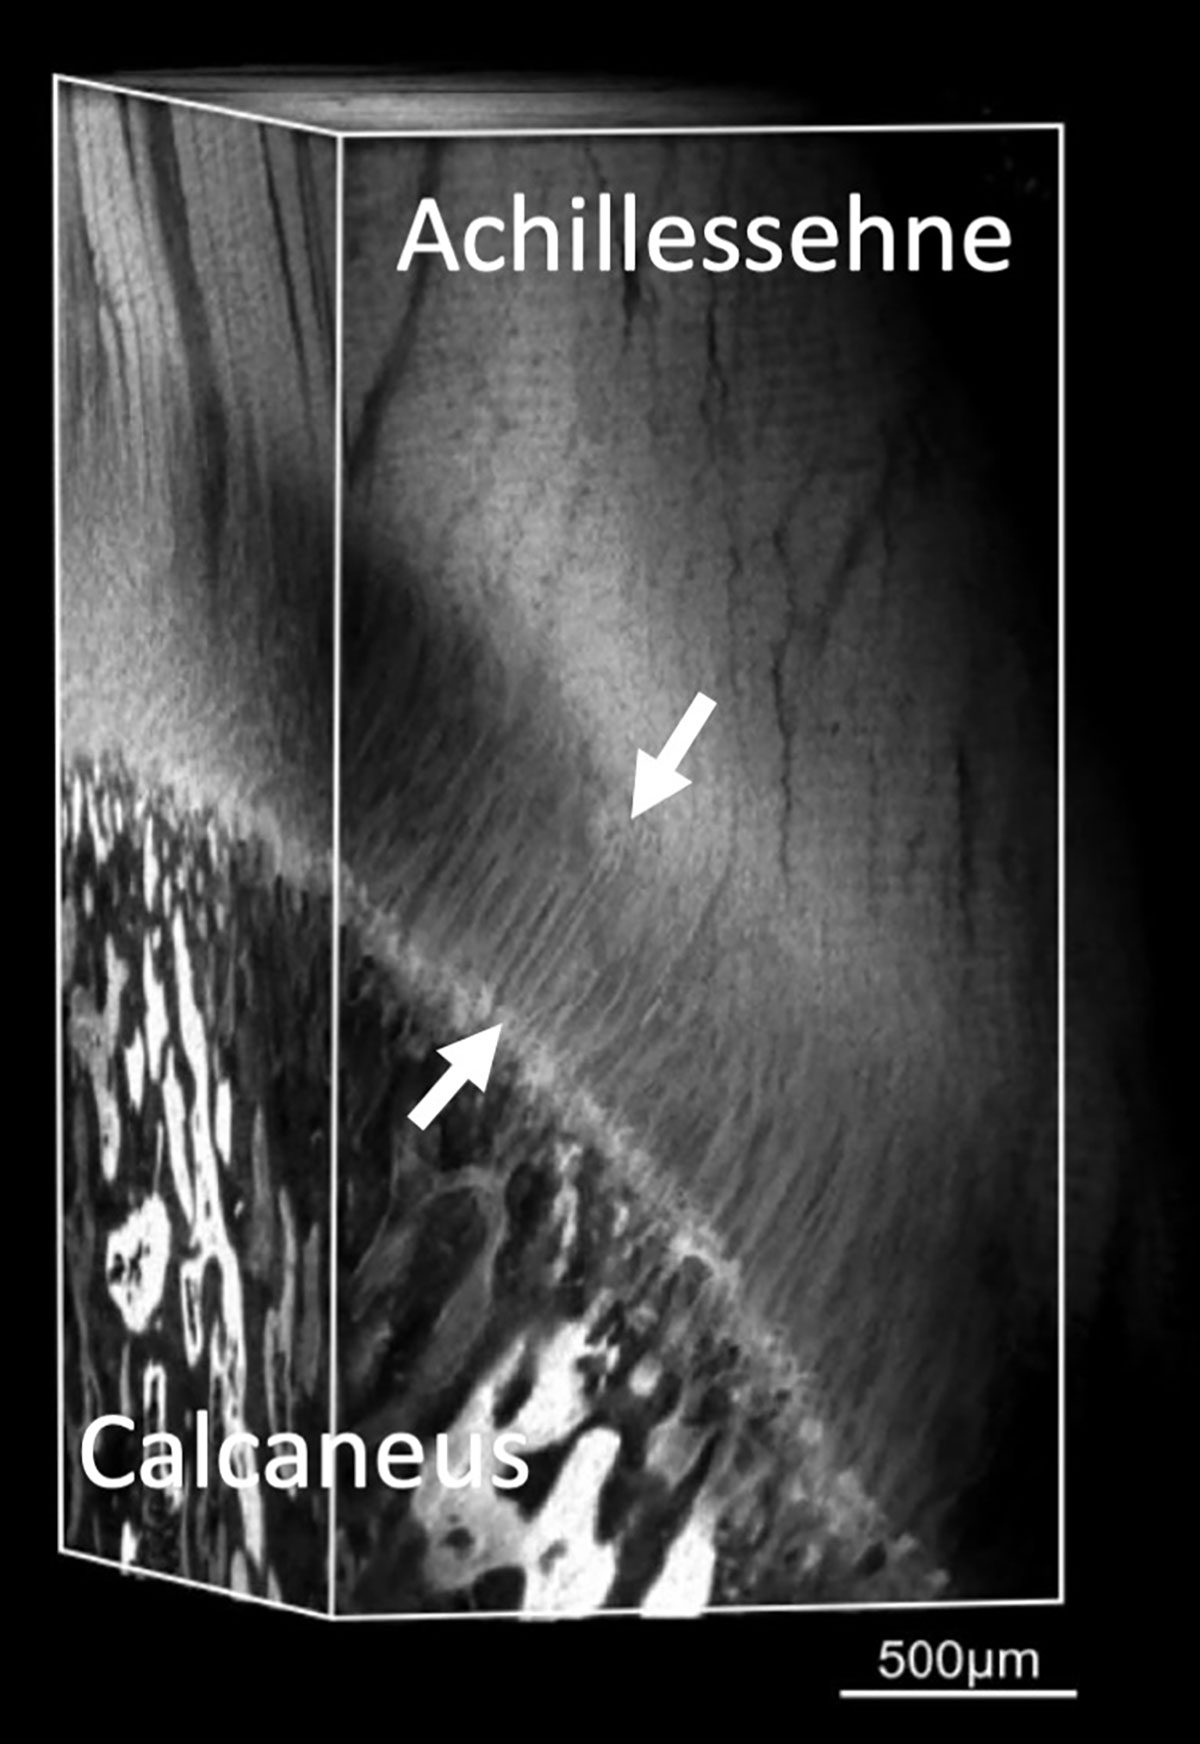

Um den mikrostrukturellen Aufbau zu charakterisieren, wurden die Proben mittels konfokaler Multiskalen-Bildgebung, Elektronenmikroskopie und hochauflösender Mikrocomputertomographie untersucht. Bei den Untersuchungen zur Mikrostruktur zeigte sich auf Basis dieses neuartigen µ-CT-Verfahrens und konfokaler Fluoreszenzmikroskopie, dass in der ca. 500 µm breiten Interfacezone (Abb. 2) sowohl die Faserstärke als auch deren biomolekulare Zusammensetzung gegenüber dem Sehnengewebe erhebliche Unterschiede aufweist. Im Gegensatz zu Knochen und Sehne, bei der Kollagen Typ I die Hauptkomponente darstellt, ist im Bereich der Enthese vorwiegend Kollagen Typ II nachweisbar (Abb. 3 und 4). Außerdem ändert sich der Faserdurchmesser im Sehnengewebe von 105 µm im Mittel (± 21 µm) auf deutlich dünnere mittlere Faserdurchmesser von ca. 13 µm (± 4 µm) (Abb. 2 und 3). Gleichzeitig fächern sich diese Interfacefasern mit Winkelwerten von bis zu 15° auf, bevor sie am Knochen ansetzen (Abb. 5).

Die Anheftung an den Knochen erfolgt dabei entlang einer ossären Oberfläche, deren Kontaktzone auf Grund der rauen, lakunenartigen Strukturierung erheblich vergrößert wird und die Interface-Fasern sich so mit dem Knochen regelrecht verzahnen. Die Spreizung der Interface-Fasern und die Verzahnung im Bereich der Kontaktzonen vergrößern die Fläche zusätzlich, über die die Kräfte übertragen werden, wodurch die Befestigungen belastbarer und resilienter werden auf Grund der damit verbundenen Reduktion der Spannungskonzentrationen [8]. Eine weitere wichtige Folge der Spreizung und Auffächerung der Fasern ist, dass die Kräfte in verschiedenen, z. T. vergleichsweise flachen Winkeln übertragen werden können und damit eine weitere Reduktion der Spannungsspitzen erfolgt. Entsprechend stellt die Spreizung und Auffächerung der Interfacefasern im Bereich der Knochenkontaktzone ein essentielles Schlüsselmerkmal dar, das die hohe Belastbarkeit und Resilienz der Enthese erklärt und entsprechend Rupturen im Bereich des Interfaces durch Minimierung von kritischen Spannungsspitzen verhindert werden.